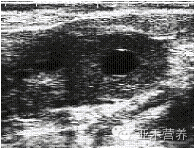

2.4 黃體囊腫聲像圖

圖4顯示該病牛左側(cè)卵巢增大,邊緣不整齊,卵巢中央有一較大、圓形液性無回聲暗區(qū),其壁較厚,界限清晰,表現(xiàn)為強(qiáng)回聲光帶。

黃體囊腫牛的B超影像圖觀察結(jié)果顯示,黃體囊腫略突出于卵巢表面,表面回聲光滑,囊內(nèi)出現(xiàn)液體暗區(qū),壁厚、黃體囊腫影像邊緣光滑有清晰的輪廓,內(nèi)部可見棉紗樣回聲或形態(tài)不規(guī)則的光團(tuán),內(nèi)壁不光滑,出現(xiàn)低淡光點(diǎn)。對(duì)患牛間隔7 d~14 d,用B超復(fù)檢的結(jié)果顯示,囊腫位置及結(jié)構(gòu)幾乎沒有變化,尺寸大小沒有變化。

圖4 黃體囊腫聲像圖

Fig.4 An ultrasound image of an luteal ovarian cysts